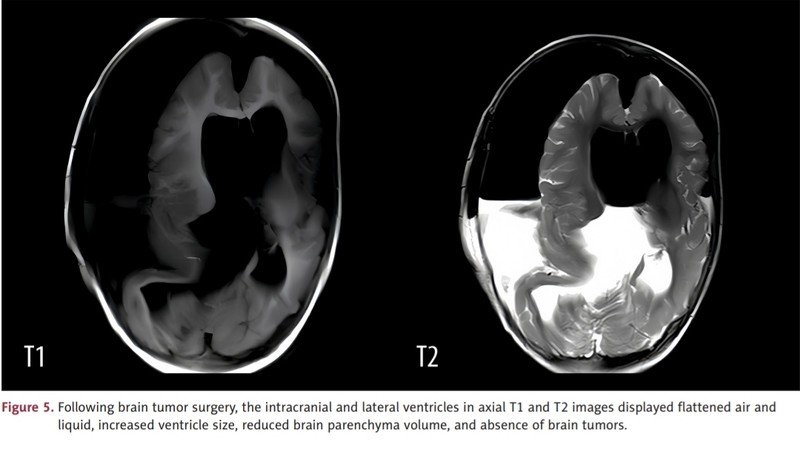

Dokter di China melaporkan kasus seorang anak perempuan berusia 1 tahun lahir dengan satu janin yang 'terperangkap' di dalam kepalanya. Ahli bedah langsung melakukan operasi karena pasien mengalami pembengkakan kepala parah, tetapi ia meninggal dua minggu kemudian karena kerusakan pada otaknya. (Foto: American Journal of Case Reports.)

Dokter di China melaporkan kasus seorang anak perempuan berusia 1 tahun lahir dengan satu janin yang terperangkap di dalam kepalanya. Ahli bedah langsung melakukan operasi karena pasien mengalami pembengkakan kepala parah, tetapi ia meninggal dua minggu kemudian karena kerusakan pada otaknya. (Foto: American Journal of Case Reports.)